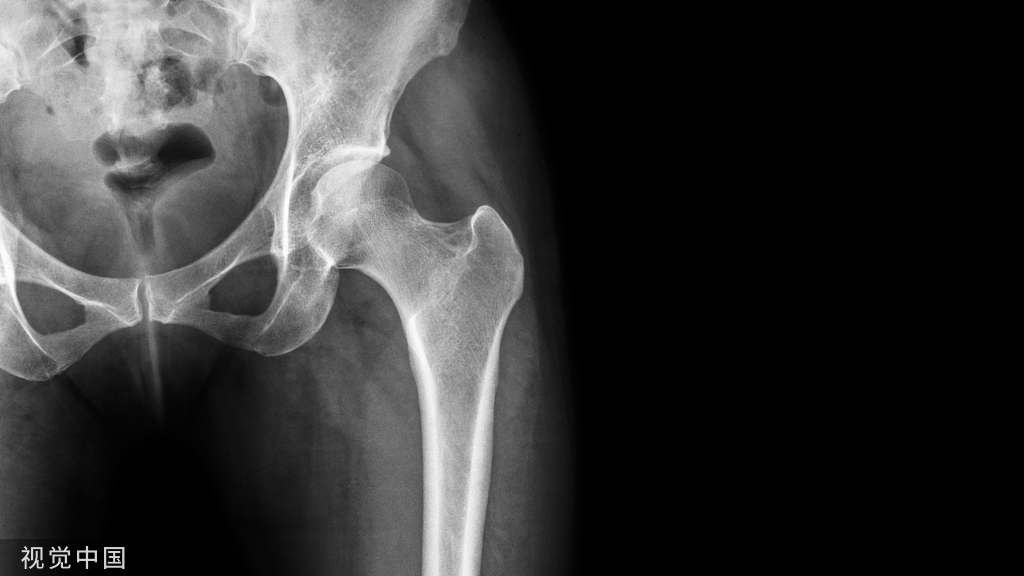

骨折生长也有“光合作用”?听听骨科医生怎么说!